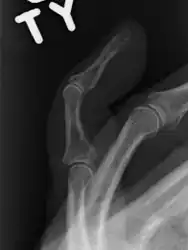

Mallet finger of the middle finger. The tip of the finger bends downwards while the other fingers stay straight. | |

- A mallet finger without an associated fracture